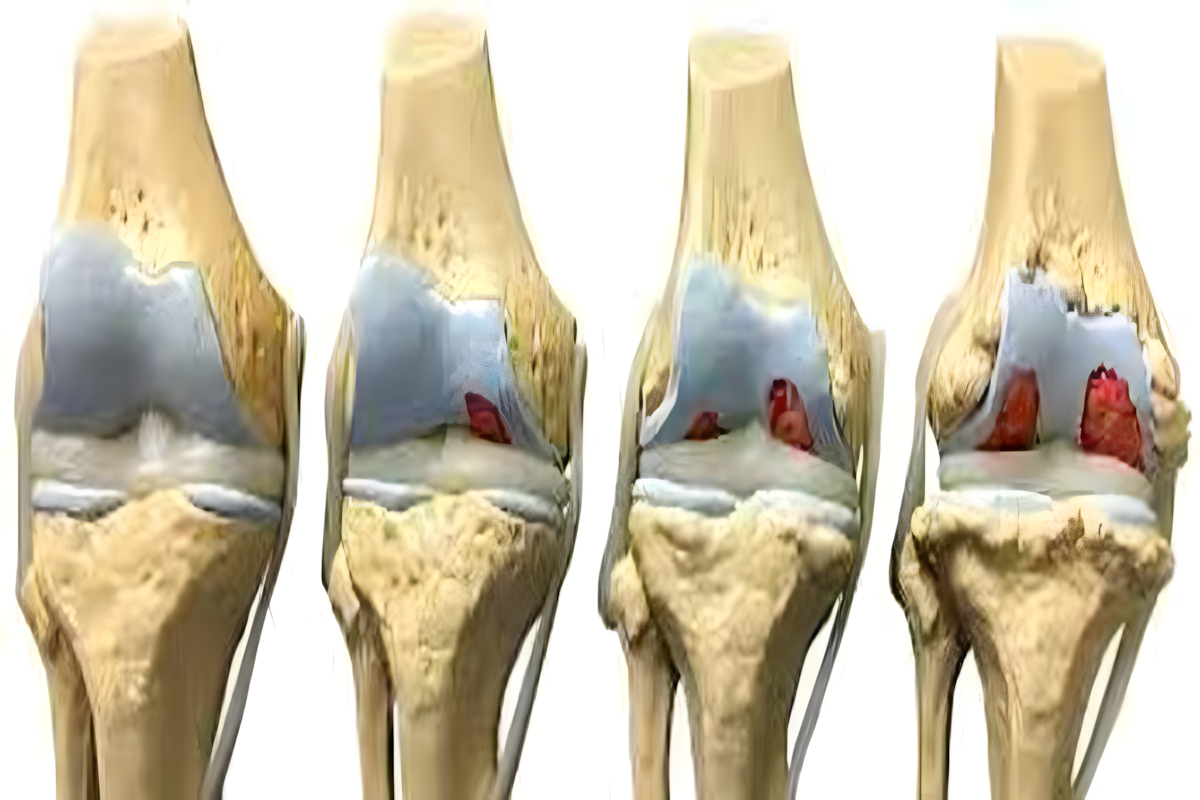

Το γόνατο αποτελεί μία από τις πιο σύνθετες και λειτουργικά σημαντικές αρθρώσεις του ανθρώπινου σώματος. Συμμετέχουν το κάτω άκρο του μηριαίου οστού, το άνω άκρο της κνήμης και η επιγονατίδα, ενώ η σταθερότητα εξασφαλίζεται από συνδέσμους, μηνίσκους και μυϊκές ομάδες.

Κατάγματα κνημιαίων κονδύλων

Τα κατάγματα κνημιαίων κονδύλων αφορούν την άνω επιφάνεια της κνήμης, η οποία συμμετέχει άμεσα στη διαμόρφωση της άρθρωσης του γόνατος.

Εμφανίζονται συχνά μετά από τροχαία ατυχήματα, αθλητικούς τραυματισμούς ή πτώσεις. Τα συμπτώματα περιλαμβάνουν πόνο, οίδημα, δυσκολία στην κίνηση και συχνά αιμάρθρο.

Ιδιαίτερη σημασία έχουν οι συνοδές βλάβες σε μηνίσκους και συνδέσμους, οι οποίες επηρεάζουν την πρόγνωση. Εκτός από τις ακτινογραφίες, σχεδόν πάντα απαιτείται αξονική τομογραφία για λεπτομερή χαρτογράφηση του κατάγματος.

Μη παρεκτοπισμένα κατάγματα μπορούν να αντιμετωπιστούν συντηρητικά με ακινητοποίηση, αποφόρτιση και σταδιακή κινητοποίηση. Παρεκτοπισμένα ή ενδοαρθρικά κατάγματα απαιτούν χειρουργική ανάταξη και σταθεροποίηση με πλάκες ή βίδες. Η φυσικοθεραπεία είναι απαραίτητη για την πρόληψη δυσκαμψίας και δευτερογενούς αρθρίτιδας.